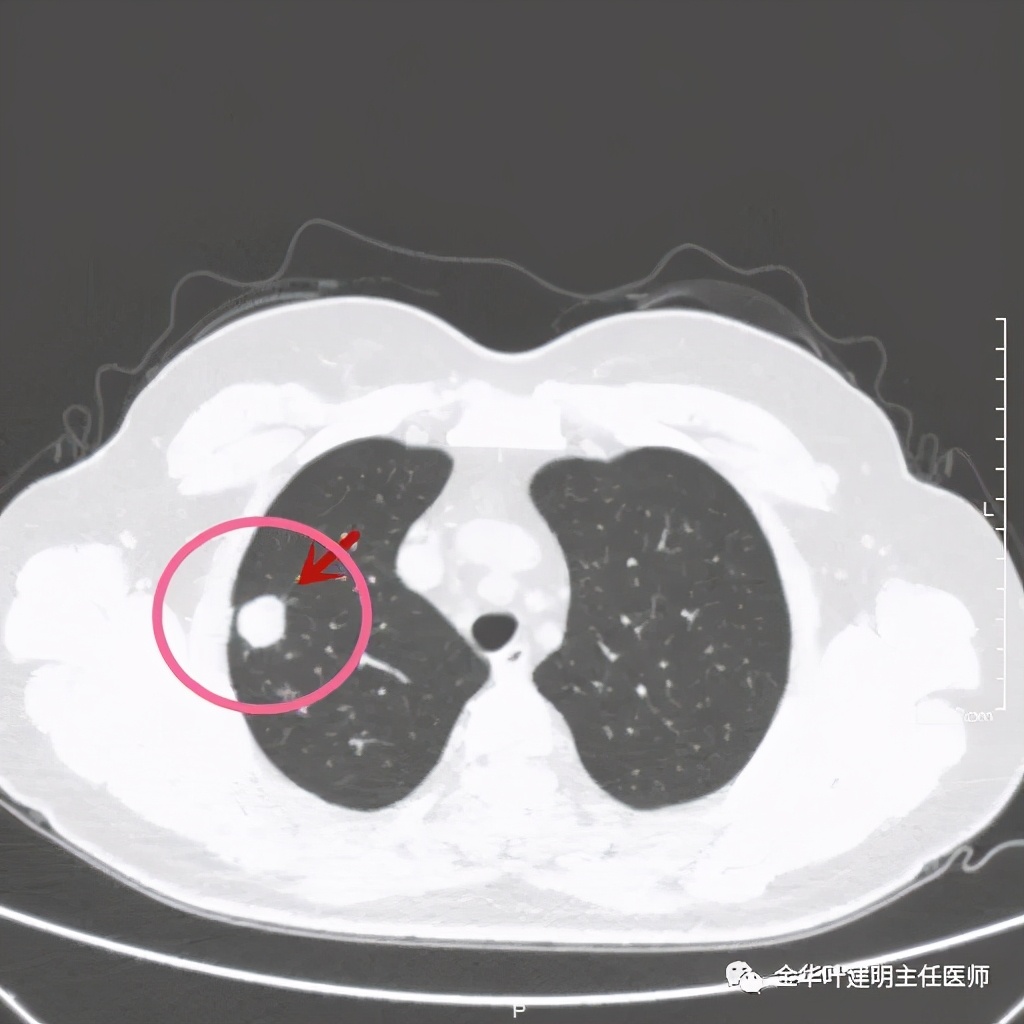

右上叶开始出现病灶,是实性的

病灶比较光滑,密度高,旁边有小的卫星灶,不清爽

绿色箭头示主病灶边有小的实性微小结节,主病灶边缘非常光滑,没有毛刺、分叶等征